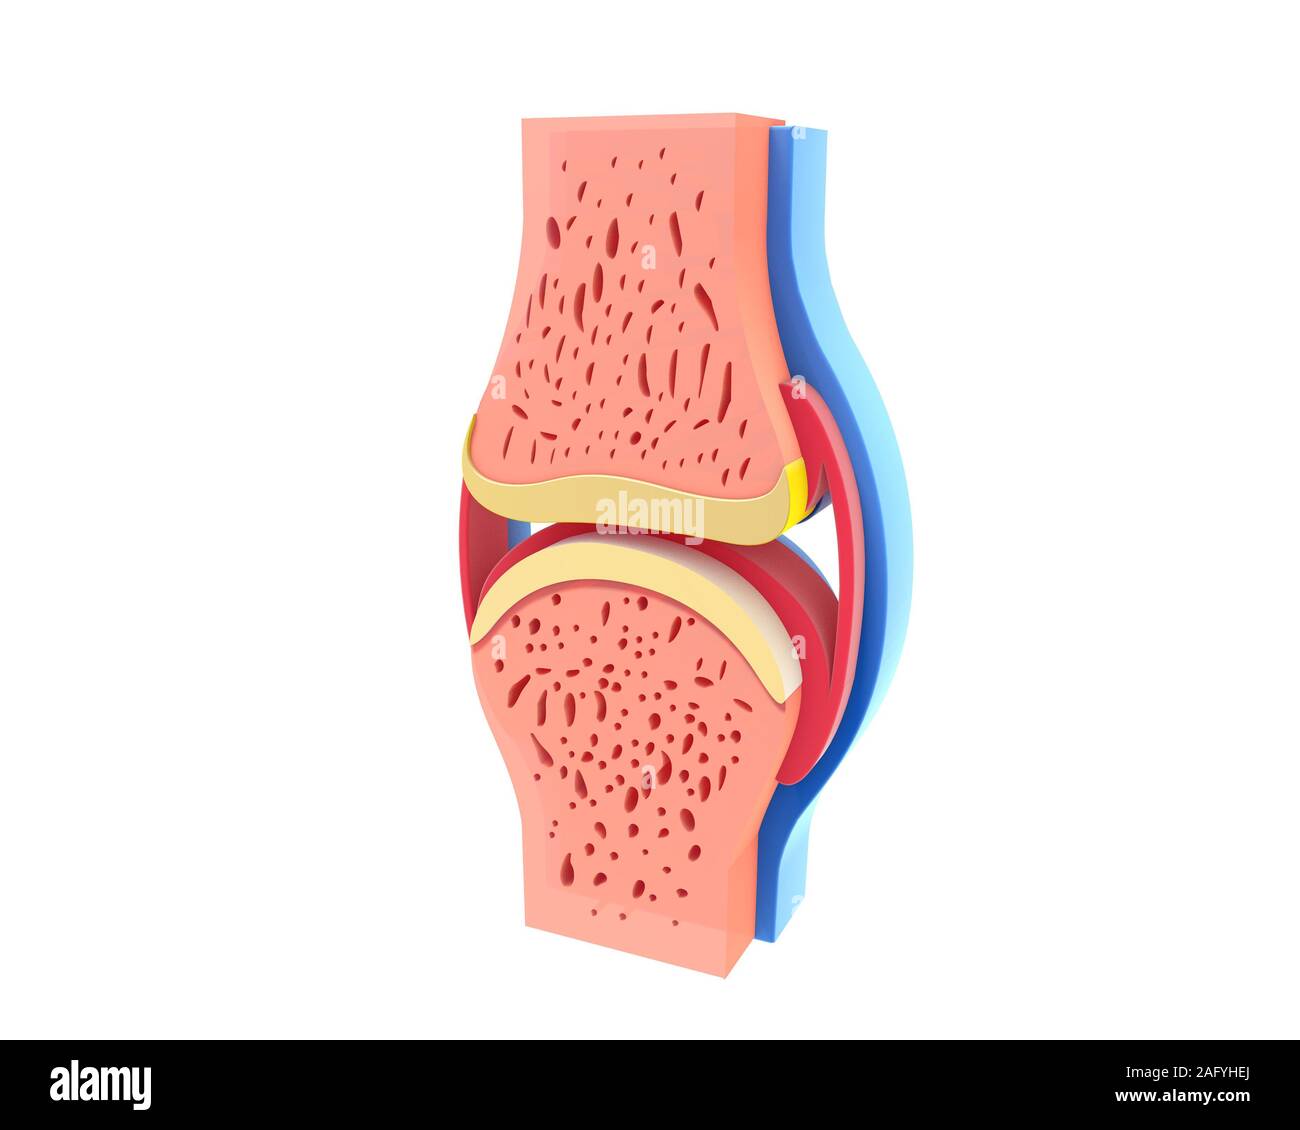

Synovial joint: joint characterized by the presence of an articular capsule filled with a viscous liquid (synovial fluid). This is the most common type of joint. Stock Photohttps://www.alamy.com/image-license-details/?v=1https://www.alamy.com/synovial-joint-joint-characterized-by-the-presence-of-an-articular-image156172846.html

Synovial joint: joint characterized by the presence of an articular capsule filled with a viscous liquid (synovial fluid). This is the most common type of joint. Stock Photohttps://www.alamy.com/image-license-details/?v=1https://www.alamy.com/synovial-joint-joint-characterized-by-the-presence-of-an-articular-image156172846.htmlRMK2281J–Synovial joint: joint characterized by the presence of an articular capsule filled with a viscous liquid (synovial fluid). This is the most common type of joint.

Articular capsule Anatomy For Medical Concept 3D Illustration Stock Photohttps://www.alamy.com/image-license-details/?v=1https://www.alamy.com/articular-capsule-anatomy-for-medical-concept-3d-illustration-image439559253.html

Articular capsule Anatomy For Medical Concept 3D Illustration Stock Photohttps://www.alamy.com/image-license-details/?v=1https://www.alamy.com/articular-capsule-anatomy-for-medical-concept-3d-illustration-image439559253.htmlRF2GF3J8N–Articular capsule Anatomy For Medical Concept 3D Illustration

3d illustration of healthy and spherical synovial joint. In four representations standing and isolated on white background. Stock Photohttps://www.alamy.com/image-license-details/?v=1https://www.alamy.com/3d-illustration-of-healthy-and-spherical-synovial-joint-in-four-representations-standing-and-isolated-on-white-background-image336823258.html

3d illustration of healthy and spherical synovial joint. In four representations standing and isolated on white background. Stock Photohttps://www.alamy.com/image-license-details/?v=1https://www.alamy.com/3d-illustration-of-healthy-and-spherical-synovial-joint-in-four-representations-standing-and-isolated-on-white-background-image336823258.htmlRF2AFYHE2–3d illustration of healthy and spherical synovial joint. In four representations standing and isolated on white background.